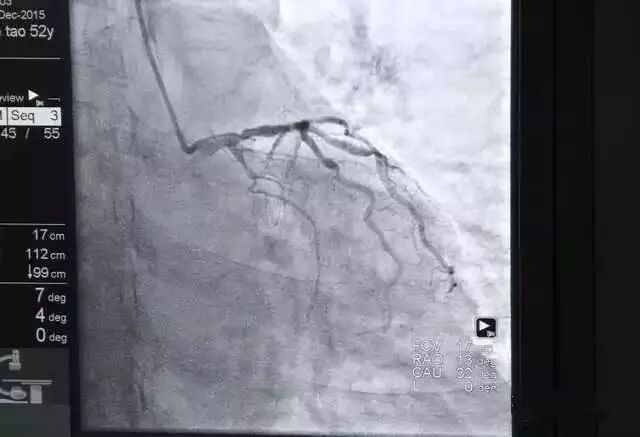

使用环柄注射器推入造影剂,通过X光透视可在电脑屏幕上显示血管形状;

在一路抵达目的地的过程中,医生需要通过X光透视来掌握情况,通过导管推入造影剂,这种特殊的液体可以在X光下清楚的显示血管粗细及走向,从而找到闭塞病变部位,也就是常说的导致血管堵塞的“罪犯血管”。